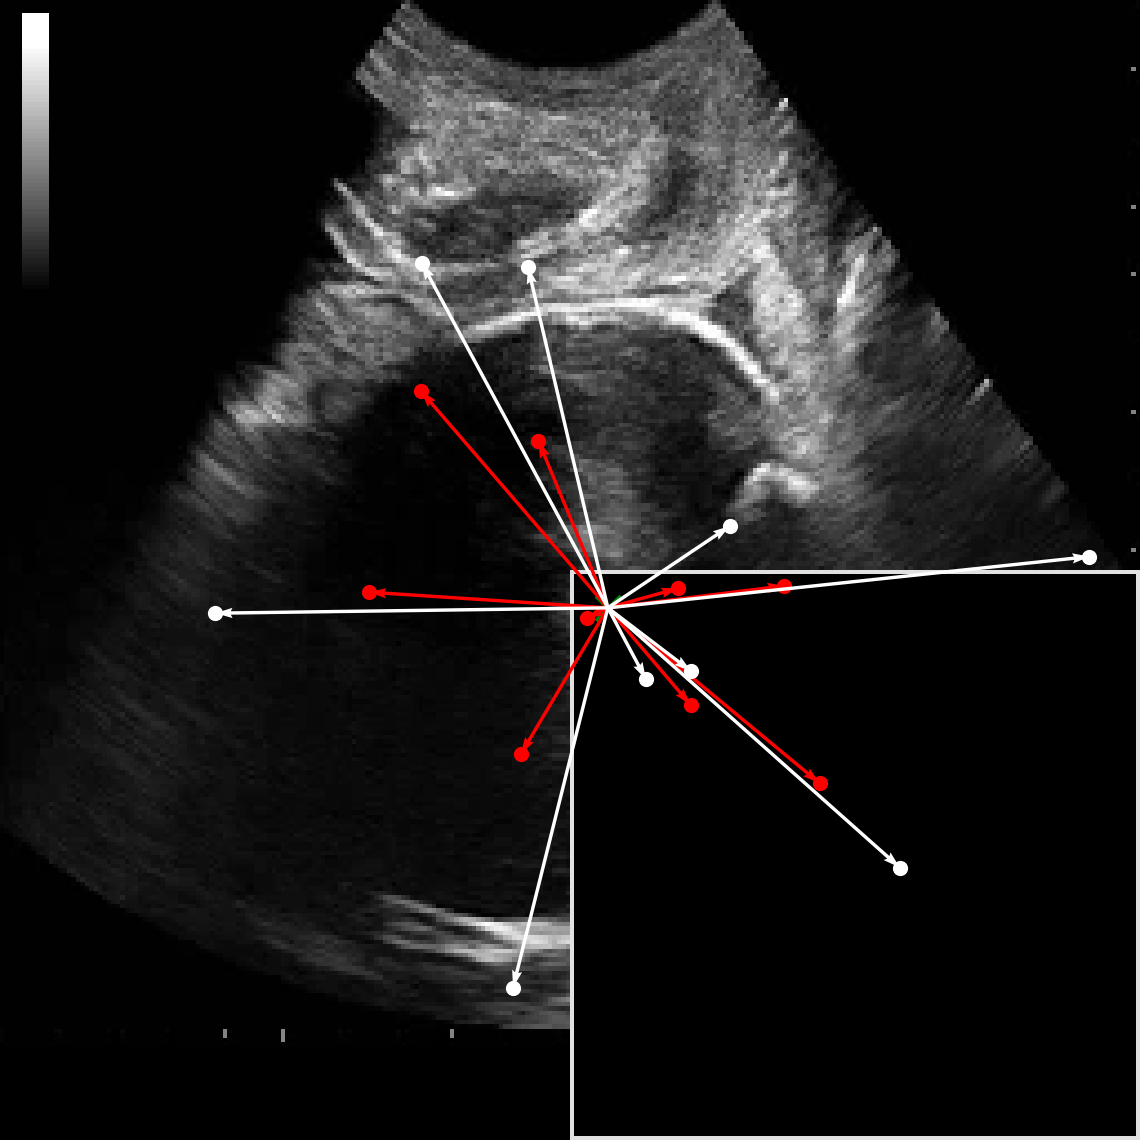

In practical clinical settings, medical images are often incomplete or degraded due to occlusions, artifacts, or limited fields-of-view. Therefore, a reliable segmentation model must be robust to missing spatial context and capable of inferring anatomical structures from partially observed inputs. To evaluate this critical property, we conducted a masking experiment using the FH-PS-AoP dataset. In this experiment, we systematically removed one quadrant from the input image, top-left, top-right, bottom-left, or bottom-right, and evaluated the performance of DAUNet compared to the baseline UNet.

Figure 7 presents a comprehensive visual comparison of the predicted offset maps and segmentation masks under each masking condition. The first column shows the original (unmasked) input along with its corresponding predictions, while subsequent columns depict the results for each of the masked quadrants.

DAUNet demonstrates markedly higher resilience to missing context compared to UNet. Its predicted offset maps remain dense and structured, with vectors that preserve anatomical directionality even when significant regions of the input are absent. This behavior reflects DAUNet’s ability to infer context from the remaining visual cues. In contrast, UNet exhibits sparse or disoriented offsets in the masked scenarios, indicating reduced spatial awareness and compromised localization.

To better understand this phenomenon, we analyzed the receptive fields of both models. For a representative pixel, we visualized its corresponding receptive area contributing to the output. In UNet, the receptive field is fixed and grid-constrained (refer to second row of Figure 7), making it sensitive to occlusions. On the other hand, DAUNet leverages deformable convolutions to dynamically adjust its receptive field based on the visible content. This adaptability is evident in the red and white arrows in the fourth column of Figure 7, where DAUNet modifies its offset patterns to account for the masked input.

The segmentation masks in third and fifth rows of Figure 7, further substantiate these findings. DAUNet consistently produces anatomically plausible segmentations of both the fetal head (green) and pubic symphysis (red), with minimal degradation even under 25% missing input. The output contours remain smooth, accurate, and well-aligned with ground truth boundaries. In contrast, UNet’s performance deteriorates noticeably, with fragmented or distorted segmentations, especially around the fetal head, as indicated by white arrows in the figure.

These results highlight the efficacy of DAUNet’s architectural innovations. The proposed combination of deformable convolution and SimAM attention allows the model to effectively reason over the visible context and compensate for spatial omissions. This robustness to incomplete inputs makes DAUNet well-suited for deployment in real-world medical environments, where noise, occlusions, and partial data are common challenges.